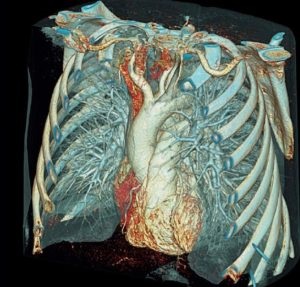

Az egyedülálló ez a viszonylag új eljárás, mellkas CT, hogy az egyik vizsgálatban, az állam a különböző szervekben és szövetekben megfogalmazni a diagnózis pontosan. Tény, hogy a képalkotó ebben az esetben helyettesíthetik több orvosi diagnosztikai módszerek, beleértve az X-sugarak, a mellkas, DEHO-CT, angiográfia. Hogy ez a kutatás, és amely lehetővé teszi, hogy a patológia?

A komputertomográfia a mellkas, hogy értékelje az állami szervek rétegenként egy háromdimenziós kép formátumban.

A komputertomográfia a mellkas, hogy értékelje az állami szervek rétegenként egy háromdimenziós kép formátumban. Ebben - a fő különbség a többi diagnosztikai eljárások. A vastagsága az egyik réteg lehet 1 mm -, és így még a nagyon kis patológia látható.

Vegye figyelembe, hogy egyes külföldi országokban, komputertomográfia a mellkas váltotta hagyományos röntgen és mellkas röntgen, mint a fő módszer a rák kimutatására. Ezt könnyen azzal a ténnyel magyarázható, hogy a CT thorax feltárja a kialakulását körülbelül 5 mm-es, míg a X-ray meghatározott eredmény csak akkor látható, abban az esetben a mérete eléri a 10 mm-es.